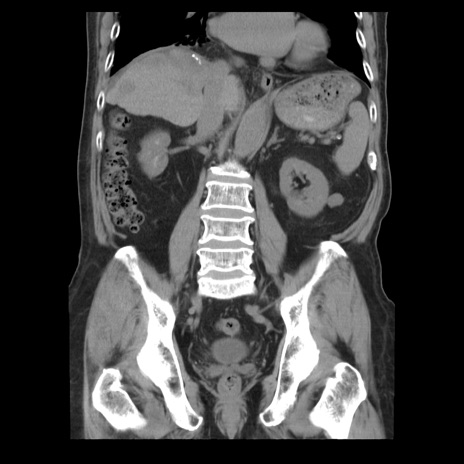

症例21(冠状断像)

【症例】70歳代男性

【主訴】腹痛

【現病歴】肝硬変・肝細胞癌にてかかりつけの方。約9時間前に食後より腹痛出現。症状が徐々に増悪し、嘔吐出現したため来院。

【既往歴】肝硬変、肝細胞癌(RFA、TACE後)

【身体所見】意識清明、表情苦悶様、BT 36℃、BP 129/78mmHg、P 88bpm、SpO2 97%(RA)、右上腹部から心窩部にかけて圧痛あり、反跳痛なし、筋性防御あり。

【データ】WBC 5800、CRP 0.16